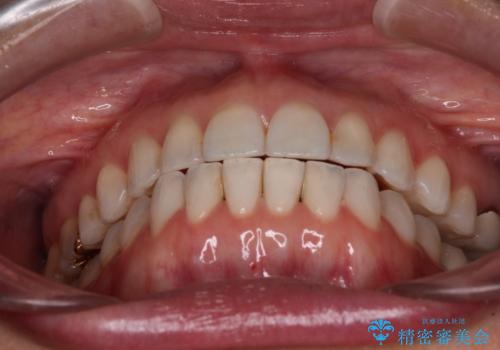

ちょっとしたデコボコをしっかりと改善したい インビザライン矯正

- 前歯のデコボコと上下スペースと前歯の隙間を気にして来院された患者様です。

目立たない装置を希望とのことでインビザラインにより、デコボコを解消しつつ、上下の前歯の隙間を閉じていくこととしました。

デコボコはあっという間に解消されましたが、上下前歯の隙間がなかなか解消されませんでした。

飲み込みの際に舌を前方に突出する癖があり、飲み込みの度に前歯に強く接触していたため、上下前歯の隙間が維持されていました。

舌の訓練を徹底していただいたことで、徐々に隙間は解消され、きれいな歯列に整えることができました。